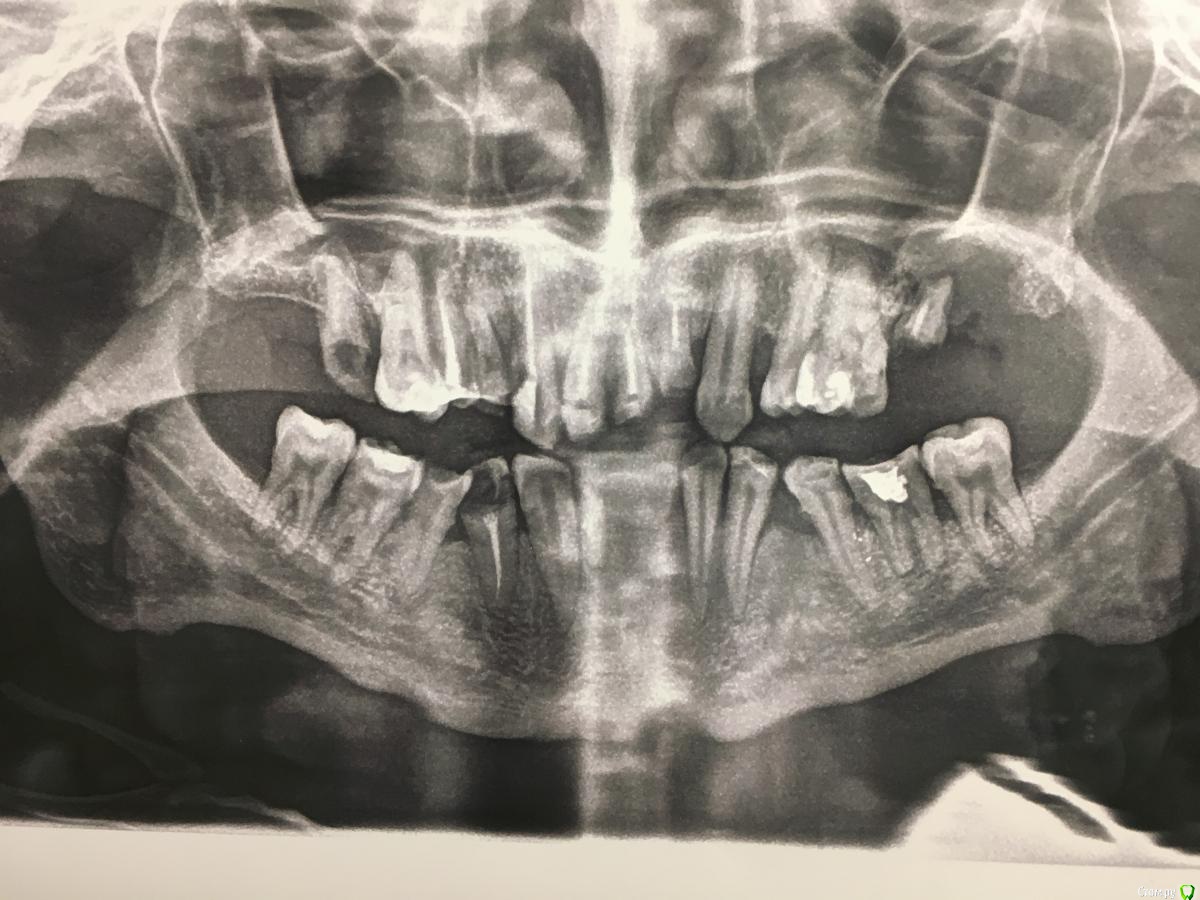

StomTYV Опубликовано 16 июня, 2018 Поделиться Опубликовано 16 июня, 2018 Добрый вечер. Коллеги, приходилось ли вам протезировать пациентов с дцп? Впервые с таким сталкиваюсь. Диагностические оттиски получилось снять, как зубы препарировать при таком заболевании не представляю. Пациент хоть и старается, все равно не произвольно дёргается в кресле. Пациент принимает: цельбрализин, баклафен, картаксен, медакаум. Ссылка на комментарий

AndyAndy Опубликовано 17 июня, 2018 Поделиться Опубликовано 17 июня, 2018 Если учитывать, что седации нет. Возможно ли протезировать такого пациента, учитывая объём работы?Сомнительно. Попробовать конечно же надо. Я делал одиночные коронки - нормально прошло, но в таком случае как у вас.... там же ещё подготовка должна быть к протезированию. Сколько лет пациенту? Ссылка на комментарий

Pavel-Pskov Опубликовано 19 июня, 2018 Поделиться Опубликовано 19 июня, 2018 Скорее всего самые проблемы будут при определении соотношения челюстей, вот где жесть начнется. Был опыт, всё очень приблизительно, Ссылка на комментарий

Pavel-Pskov Опубликовано 20 июня, 2018 Поделиться Опубликовано 20 июня, 2018 Я ставил вверху четыре импланта и на них 10 ед м.к. мост. протез. ЦС определил очень приблизительно, попросил техника накидать побольше керамики и дорабатывал во рту, типа как в анекдоте " напильником". не идеально, но внизу пластмассовый мост. протез от 43 до 33, так что компромисс приемлим. Что буду делать когда 33 и 43 уйдут-большой вопрос, предпочитаю пока об этом не думать. Ссылка на комментарий